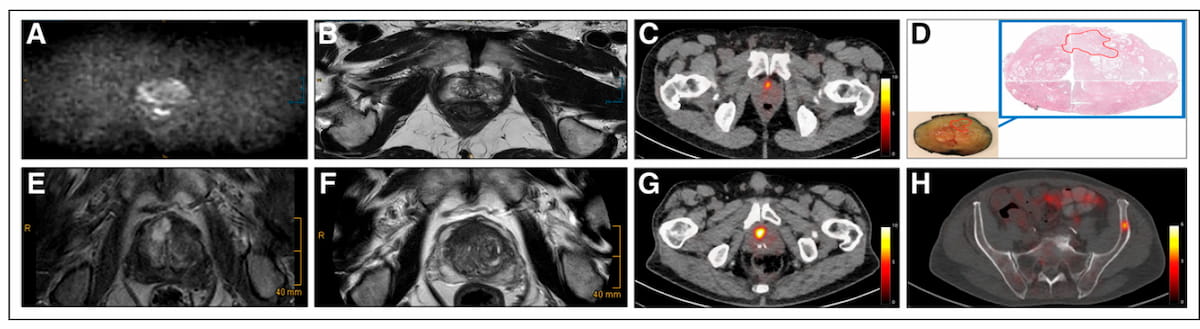

Utilizing the AI-enabled TrackPSMA to monitor the effectiveness of radioligand therapy for prostate cancer may allow more timely decisions to adjust treatment dosage or switch to a more effective modality.

In a prospective study comparing PSMA PET/CT and mpMRI for biopsy- and imaging-naïve men with suspected prostate cancer (PCa), PSMA PET/CT led to altered management in 34 percent of confirmed cases of PCa.

In a new review from the European Society of Urogenital Radiology (ESUR), researchers discuss the merits and limitations of PSMA PET/CT and whole-body MRI (WB-MRI) for patients with advanced prostate cancer.

In the 160-patient study comparing 18F-PSMA 1007 PET/CT and 18F-NaF PET/CT, the use of 18F-PSMA PET/CT led to 38 patients being restaged as having more advanced prostate cancer.

PSMA PET offered 18 percent higher accuracy for detecting biochemical recurrence of PCa in contrast to mpMRI, according to findings from a 67-study meta-analysis.